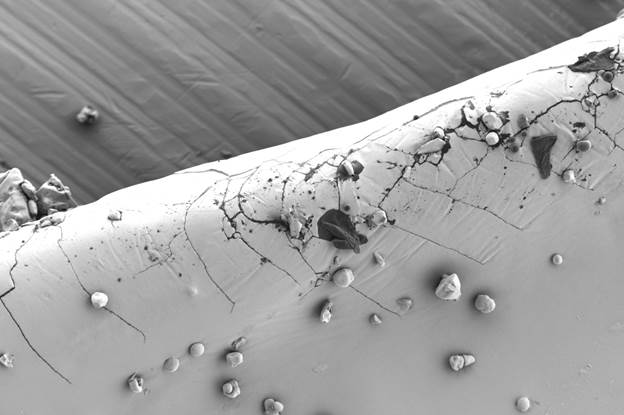

Так, при плановой проверке качества капсул с сульфатом глюкозамина с помощью оптического микроскопа были обнаружены мелкие дефекты на поверхности. Последующий анализ на СЭМ при высоком увеличении выявил микротрещины и прикрепленные пластинчатые частицы неправильной формы (рис. 1а). Морфология трещин указывала на их возможное происхождение в результате коррозии под напряжением, связанной с неравномерной сушкой покрытия и релаксацией полимерных напряжений. Инородные частицы по своей структуре (рис. 1b — чистая поверхность) отличались от матрицы капсулы.

Сопоставление с типичными микроорганизмами позволило исключить биологическую природу загрязнения; наиболее вероятным источником была признана неорганическая пыль из производственной среды или вспомогательных веществ. Эти данные послужили основой для корректировки режимов нанесения покрытия и ужесточения контроля чистоты в производственных помещениях.

Рис. 1b — Фрагмент неповрежденной поверхности капсулы (без загрязнений). Изображение получено с помощью LANSEM 30.